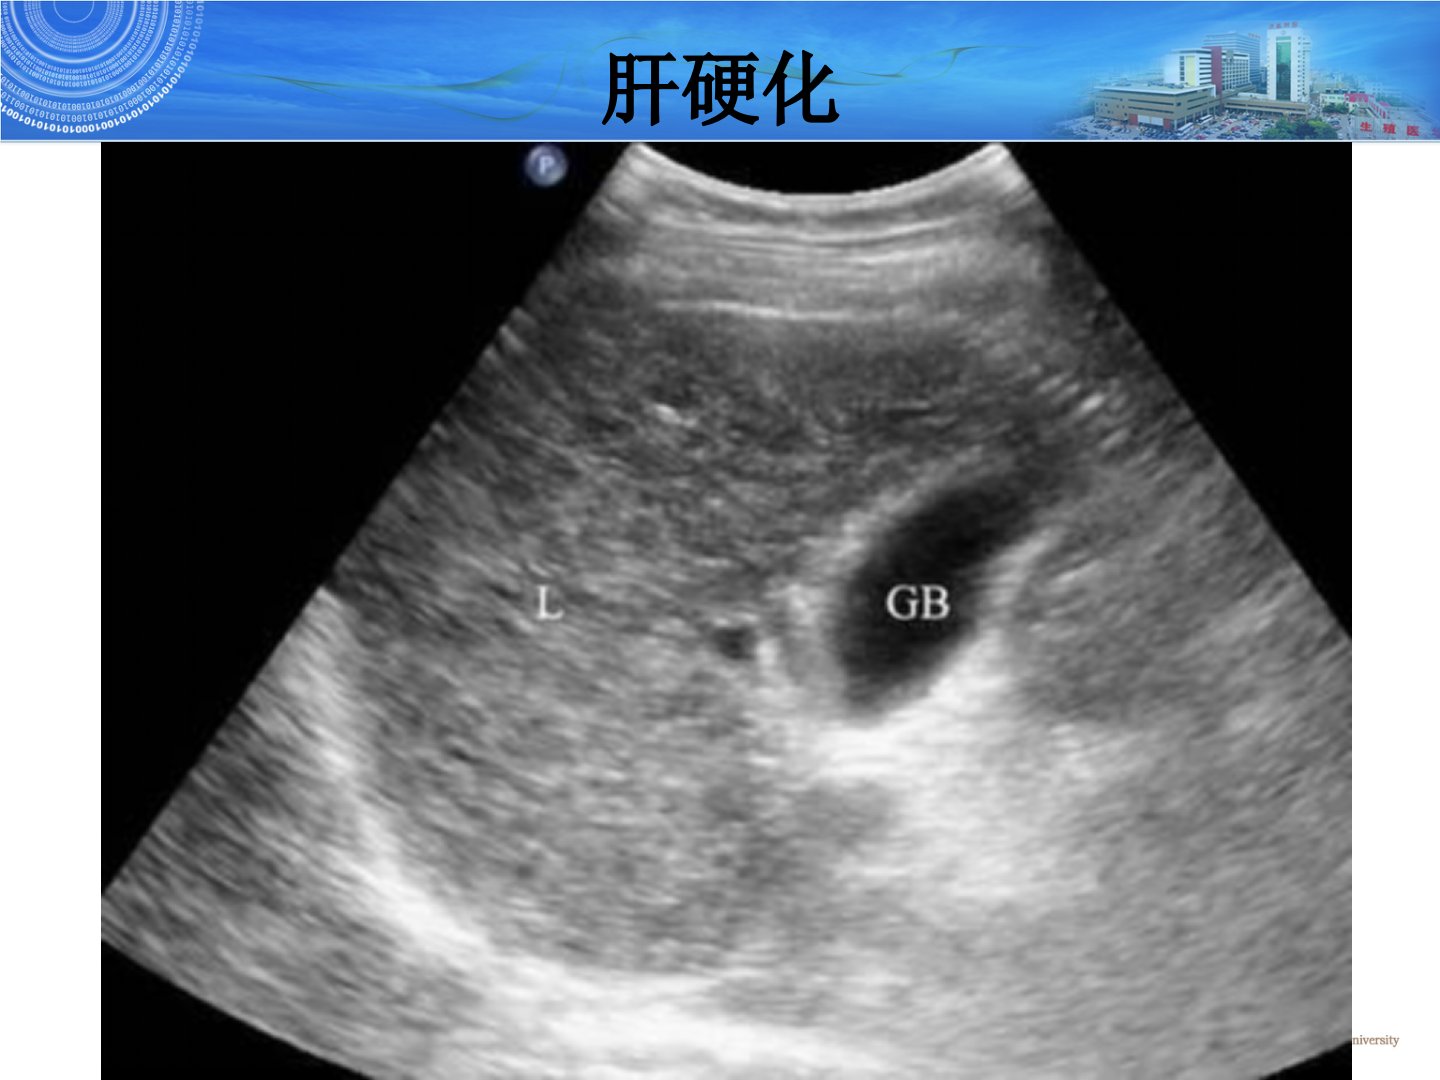

本文介绍了腹部常见疾病的超声诊断重点涵盖肝硬化、胆囊结石、急性胆囊炎及肾结石。肝硬化是常见慢性肝病灰阶超声下典型表现为肝左右叶缩小或左叶代偿性增大肝包膜锯齿状肝区回声增粗增强血管纹理紊乱脾大、腹水等;彩色多普勒可见门静脉扩张、血流速度降低肝动脉流速及RI增高肝静脉变细等。胆囊位于肝右叶胆囊窝内胆囊结石典型声像图为胆囊内强回声伴声影可随体位移动泥沙样结石则表现为胆囊后壁强回声带伴声影。急性胆囊炎多由结石嵌顿引起声像图表现为胆囊肿大、壁增厚、胆汁浑浊。肾结石超声表现为肾窦内强回声伴声影含钙结石声影显著CDFI检查可见快闪伪像超声对0305cm以上肾结石敏感性高达96。